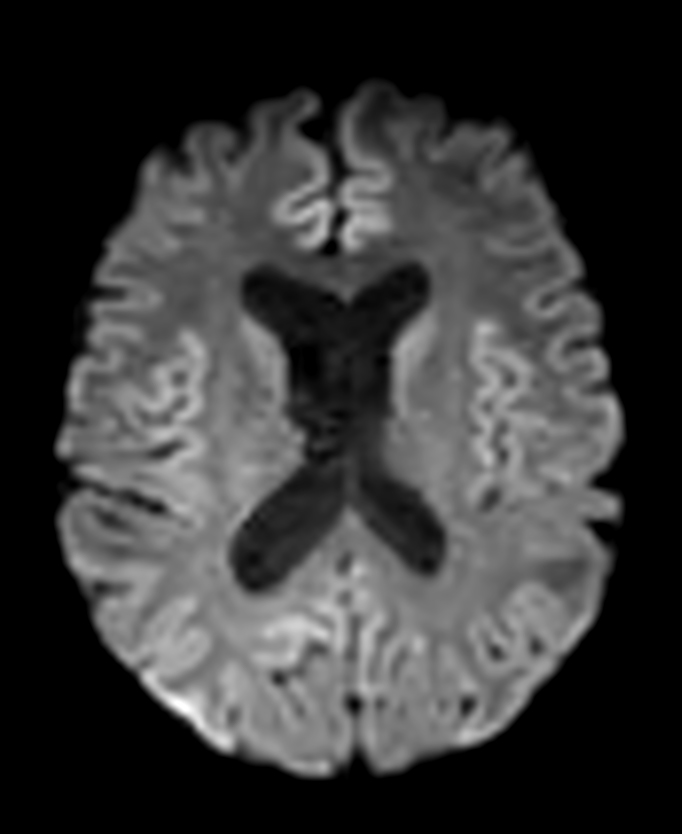

Patient with a lesion in the cerebellum. The ExamCard includes Compressed SENSE to accelerate the entire exam and techniques for motion reduced imaging (MultiVane XD), 3D imaging to acquire high resolution data in multiple directions, 3D susceptibility weighted imaging (SWIp), angiography sequences (Time-of-Flight and Contrast-Enhanced MRA with both arterial and venous phases), DTI with MultiBand SENSE to acquire a high number of diffusion directions in a short scan time and EPIC Brain to bring down any residual distortion.

DWI b1000